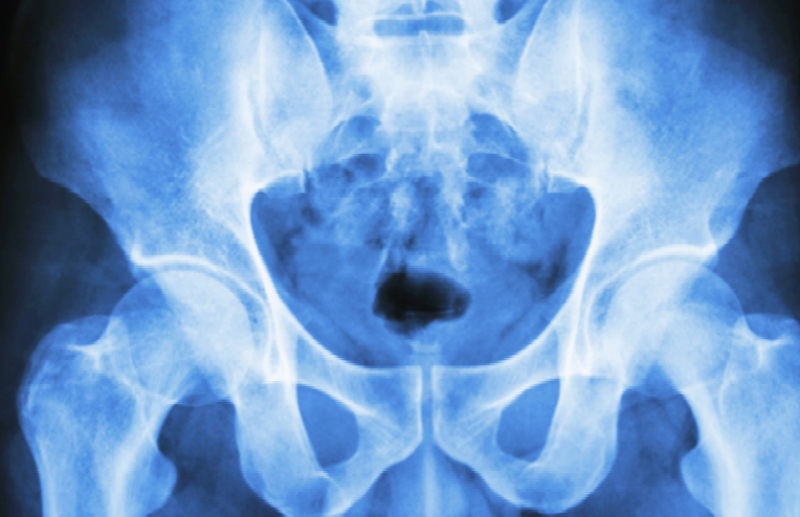

4. 고관절 골절

고관절 골절은 어떠한 외상으로 인해 대퇴골의 경부 또는 전자간부가 부러진 경우인데요. 상대적으로 뼈가 약한 노년층에서 그 발생빈도가 높습니다. 마찬가지로 고관절 골절이 일어나면 극심한 통증과 함께 움직임에 제한이 생기게 되므로, 나이가 있는 사람들의 경우 빠른 수술을 진행해야 합니다.